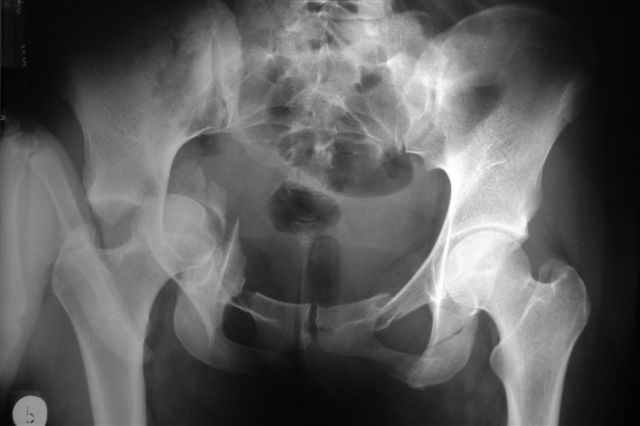

acetabular fracture

Уважаемые коллеги, Поступила 21 года барышня после автоаварии.

Интересно было бы ваше мнение какой доступ оптимален, положение на животе или на боку? Заранее признателен, Евгений И.Чекашкин